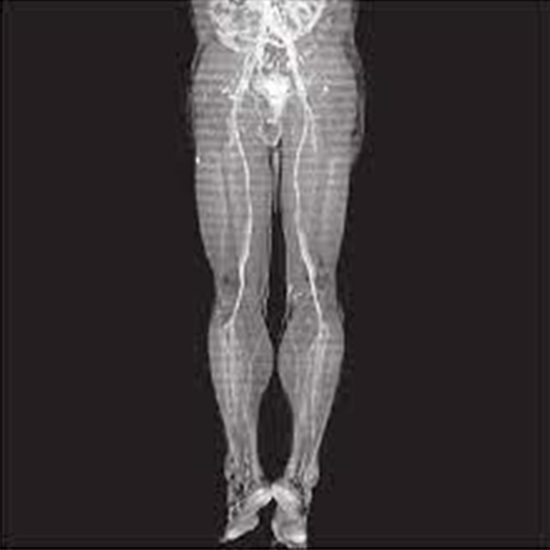

CT (Computerized Tomography) Angiography uses an iodine-rich contrast material injection and CT scanning to diagnose blood vessel problems such as aneurysms (weakening of the artery wall resulting in a bulge) and blockages in the lower extremities or lower limbs. It is carried out when there is a suspicion of insufficient blood flow to the legs, as indicated by pain while walking. It is also used when symptoms such as cramps and excessive fatigue in the legs and hips are observed while climbing stairs or walking. To detect blood vessels, a CT scan employs a large number of X-ray beams and electronic X-ray detectors.

The blood vessels appear bright white in the images after the contrast is injected into the patient's body via a catheter. Physicians use the test to diagnose blockages, aneurysms, disorganised blood vessels, and blood vessel injuries.